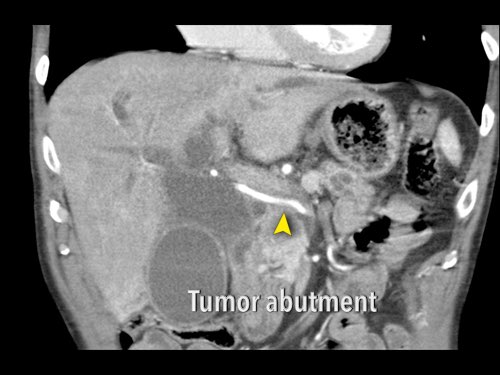

Đánh giá mức độ xâm lấn mạch máu theo chu vi được thực hiện theo từng bước 90 độ.

Tiếp xúc dưới 180 độ được gọi là áp sát (abutment) và tiếp xúc trên 180 độ được gọi là bao quanh (encasement).

Xác suất xâm lấn mạch máu là 40% đối với áp sát và 80% đối với bao quanh, có thể lên đến 100% khi khối u bao quanh hoàn toàn tĩnh mạch cửa hoặc tĩnh mạch mạc treo tràng trên (SMV).

Tái tạo mặt phẳng coronal cho thấy một khối u lớn xuất phát từ cổ tụy với kiểu phát triển xâm lấn (hình A và B).

Có hiện tượng bao quanh động mạch thân tạng 360º (mũi tên trong A).

CT axial MIP tại mức động mạch thân tạng cho thấy hẹp động mạch gan chung bị bao quanh (mũi tên), rất nghi ngờ xâm lấn.